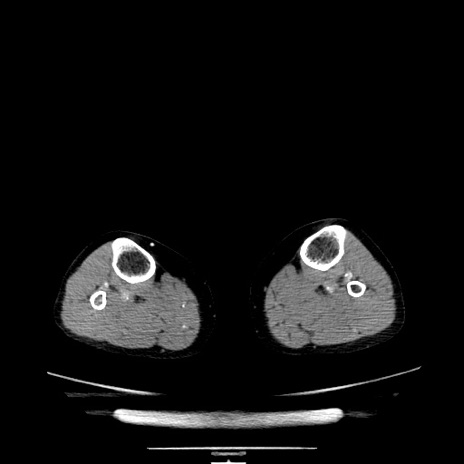

症例5(横断像)

【症例】70歳代女性

【主訴】お腹が張る

【現病歴】1週間くらい前から腹部膨満の自覚あり。昨日夜から増悪したため、本日救急外来受診。

【身体所見】意識清明、BT 36.5℃、BP 165/106mmHg、HR 80bpm、SpO2 98%、腹部:膨満、軟、自発痛・圧痛なし、触診にて不快感あり、腸蠕動音:減弱

【データ】WBC 12600、CRP 1.04